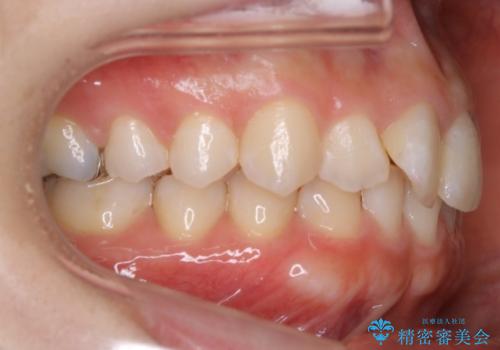

生まれつき下の前歯が1本少なく、その分のスペースを上の前歯がガタつくことで埋めているという状況でした。

上下それぞれのガタつきをとっていく過程で、歯1本分のスペースの差を、上顎の前歯のIPRで調整して並べる方法をご提案させていただきました。

稀に、乳歯が抜けてもその後に永久歯が生えてこないことがあります。生まれつき歯の元となる「歯胚」というものが欠如していることが原因で本数が少なくなることを「先天欠如」といいます。

こういったケースの治療では欠損している歯の本数分反対の顎の歯(上顎に欠損がある場合は下顎の歯)を抜歯してスペースの調整をする場合や、欠損歯の幅分のIPRを反対の顎の歯に設定することでスペースのコントロールをするという方法、欠損している歯の分のスペースを残して矯正を終了し最後にブリッジ治療やインプラントで歯の本数を増やすという方法があり、状況や患者さんの希望により選択をしていきます。